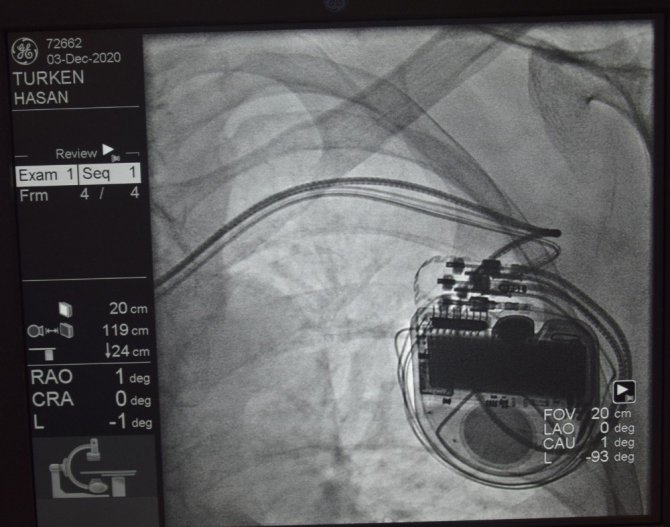

Kardiyak Resenkronizasyon tedavisi, ağır kalp hastalarının şikayetlerini azaltarak yaşam sürelerinin uzamasını katkı sağlıyor. Az sayıda merkezde yapılabilen tedavi merkezini başarı ile uygulayan Düzce Üniversitesi Hastanesi Kardiyoloji Anabilim Dalı ise tedavi ile ağır kalp yetmezliği hastalarına umut oluyor. Merkezin tedavi yöntemini duyan 78 yaşındaki Hasan Türken de hastaneye gelerek tedavi olmak için Kardiyoloji Polikliniğine başvurdu. Türken'in yapılan tetkik ve değerlendirmeler sonrası Kardiyak Resenkronizasyon tedavisi uygulanmasına karar verildi. Düzce Üniversitesi Tıp Fakültesi Kardiyoloji Anabilim Dalı Başkanı Doç. Dr. Osman Kayapınar ve ekibi tarafından yapılan operasyon sonrası sağlığına kavuşan hasta Türken, taburcu edildi.

Az sayıda merkezde uygulanan tedavi yöntemi hakkında bilgiler veren Doç. Dr. Osman Kayapınar, kalbin ileti sistemlerinde meydana gelen bazı bozuklukların, kalpte senkron kasılmayı bozarak, kalp fonksiyonlarının olumsuz etkilenmesine neden olduğuna dikkat çekti. Kardiyak Resenkronizasyon tedavisi ile üç odacıklı özel pacemaker sistemleri vasıtasıyla ventrikül içi ileti gecikmesine bağlı gelişen dissenkroniyi ortadan kaldırılabildiğini ve kalp fonksiyonlarının düzeltilerek senkron çalışmasının sağlandığını ifade eden Doç. Dr. Kayapınar, Düzce Üniversitesi Hastanesi'nde bütün kalp pili uygulamaları gibi Kardiyak Resenkronizasyon tedavisinin de (KRT) başarıyla uygulandığını vurguladı.